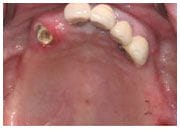

治療前